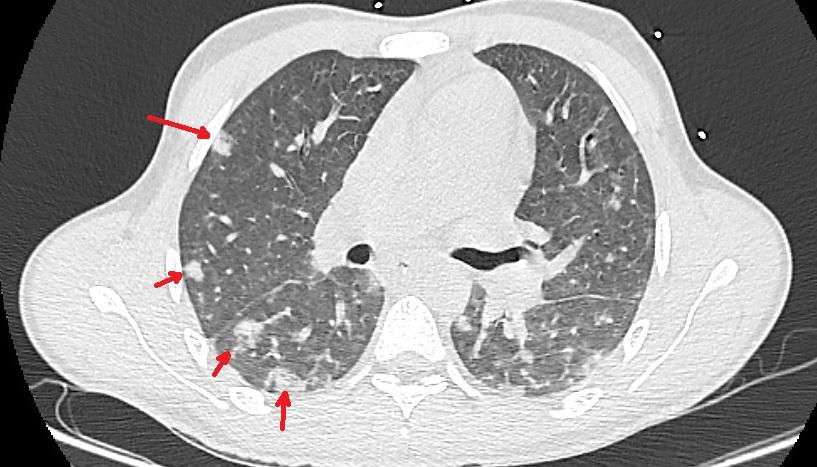

Les patients atteints du syndrome de Lemierre peuvent souvent se présenter à l'hôpital avec des preuves de lésions métastatiques dans les organes cibles [8,9]. Lorsque la thrombophlébite septique de la veine jugulaire interne (VJI) se produit, les emboles septiques formés peuvent se propager à divers sites, notamment les poumons, les articulations, le cerveau et le foie [9]. Cela peut entraîner des pathologies graves des organes qui peuvent nécessiter une intervention chirurgicale. Les poumons sont généralement les organes les plus touchés, et les patients peuvent développer une pneumonie, des empyèmes, des abcès pulmonaires, des épanchements pleuraux ou des emboles pulmonaires septiques [4,16]. Ces manifestations se traduisent souvent par des douleurs thoraciques pleurétiques, une dyspnée, une toux et une hémoptysie [37]. Lemierre lui-même avait noté que les manifestations pulmonaires étaient annoncées par « une douleur thoracique intense d'apparition brutale, une dyspnée, parfois des crachats teintés de sang ou rouillés, des frottements pleuraux, et des zones localisées de râles sous-crépitants » [3].